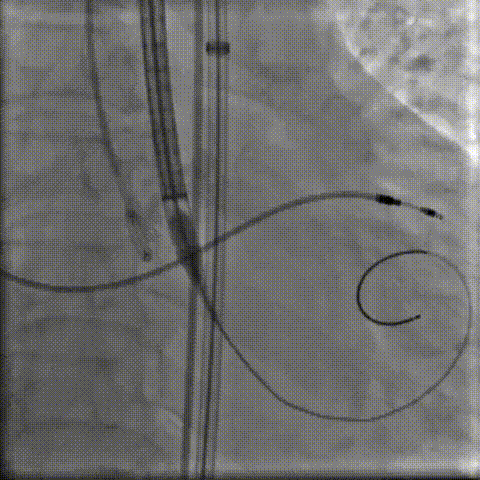

4.定位

9.gif

5.释放过程

10.gif